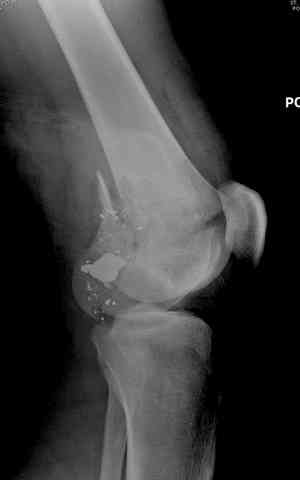

Здесь представлены несколько случаев лечения огнестрельного перелома

2 внутрисуставной перелом дистального бедра с удалением пули

Условием для обязательного удаления пули считаем ее внутрисуставное расположение из-за возможного сатурнизма, или когда во время операции она без труда удаляется, а также поверхностно расположена.

Характерным признаком травмы с низкой кинетической энергией является отсутствие "мультифрагментации и кавитации", и поэтому в данном случае лечение можно проводить любым доступным методом.